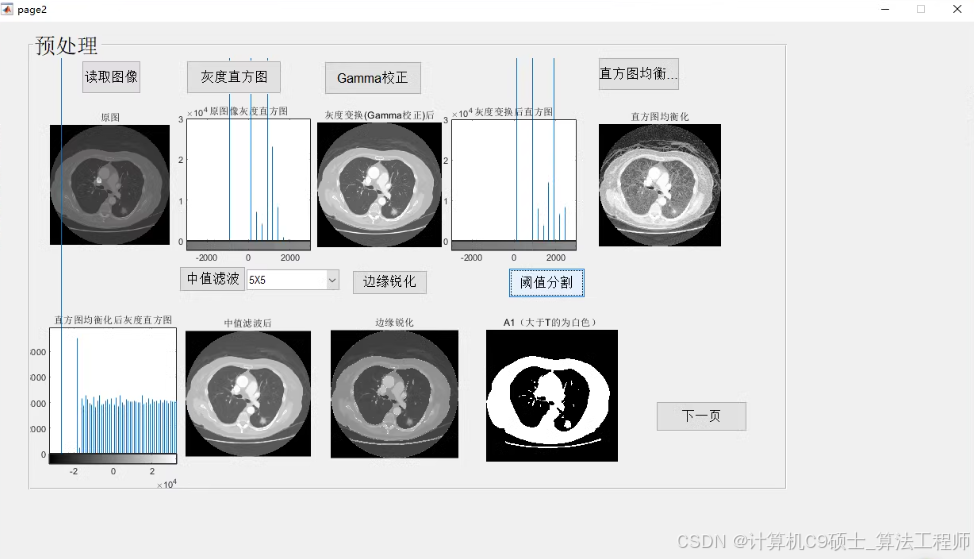

2、图像增强。对图像进行图像增强,包括Gamma矫正、直方图均衡化、中值滤波、边缘锐化;

7、做成GUI人机界面。

图像增强

GUI人机界面

图像增强:enhance_image.m对图像进行Gamma矫正、直方图均衡化、中值滤波和边缘锐化。

GUI人机界面:PulmonaryNoduleSegmentation.fig和PulmonaryNoduleSegmentation.m提供了一个用户友好的界面,方便用户进行图像处理和结果显示。